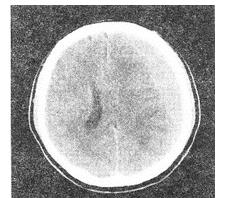

- 单项选择题 患者男性,24岁,头部被球击中,1周后出现持续性头痛、头晕,结合CT图像,最可能的诊断是()。

A、亚急性硬膜下血肿

B、硬膜外血肿

C、急性硬膜下血肿

D、脑挫裂伤

E、慢性硬膜下血肿

- A